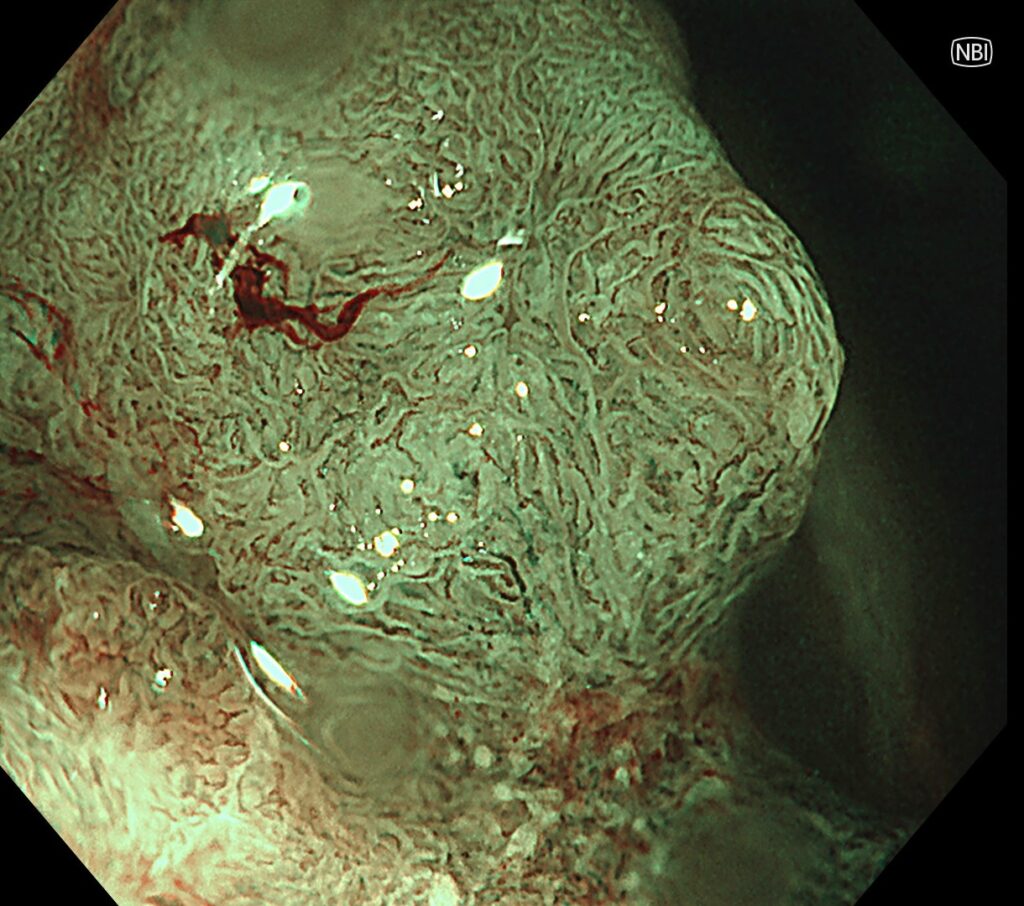

NBI拡大で、大腸癌であることを確認。